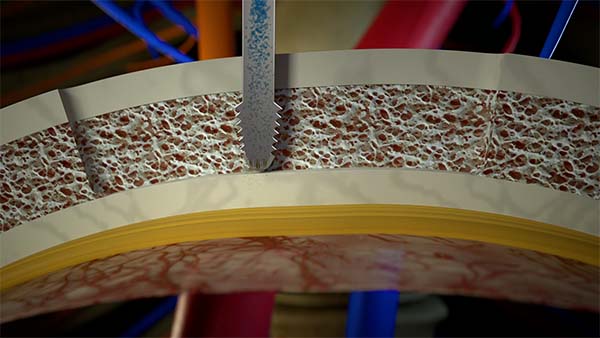

Selective osteotomies, safety on soft tissues

Selective cut preserves soft tissue. (Dura, neves and vessels)

Cold osteotomy avoids bone necrosis

Increased surgical control & flexibility in bone cutting

Micrometric cut for minimal bone loss

CAVITATION EFFECT

Maximum intra-operative visibility.

Blood-free surgical site.